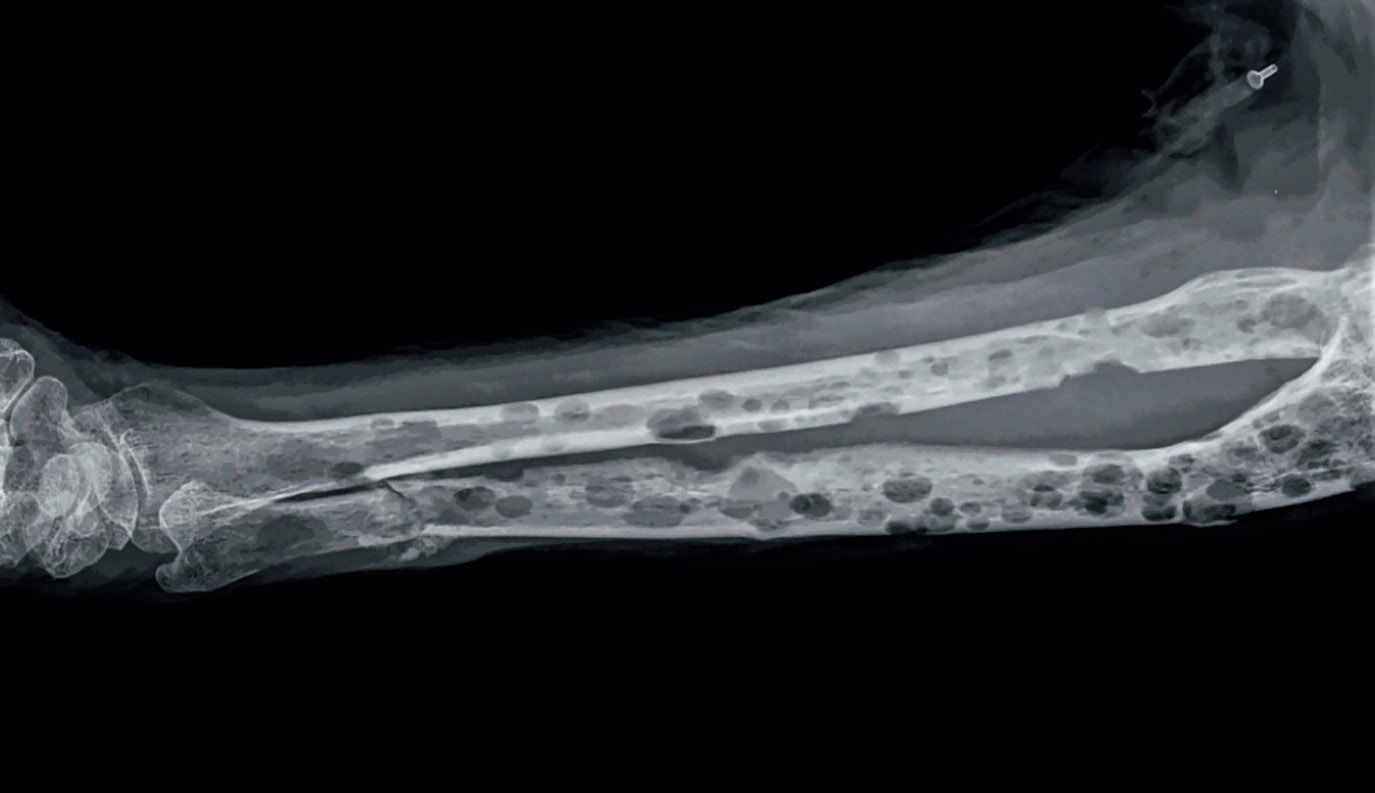

Визуальные материалы, связанные с болезнью Горхема-Стаута

Раздел: Альбом открытий